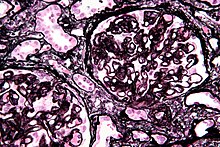

| Micrograph of diffuse proliferative lupus nephritis showing increased mesangial matrix and mesangial hypercellularity. Kidney biopsy. PAS stain. | |

Class II disease (mesangial proliferative glomerulonephritis) is noted by mesangial hypercellularity and matrix expansion. Microscopic haematuria with or without proteinuria may be seen. Hypertension, nephrotic syndrome, and acute kidney injury are very rare at this stage.[14]

Class IV disease (diffuse proliferative nephritis) is both the most severe, and the most common subtype. More than 50% of glomeruli are involved. Lesions can be segmental or global, and active or chronic, with endocapillary or extracapillary proliferative lesions. Under electron microscopy, subendothelial deposits are noted, and some mesangial changes may be present. Clinically, haematuria and proteinuria are present, frequently with nephrotic syndrome, hypertension, hypocomplementemia, elevated anti-dsDNA titres and elevated serum creatinine.[14]